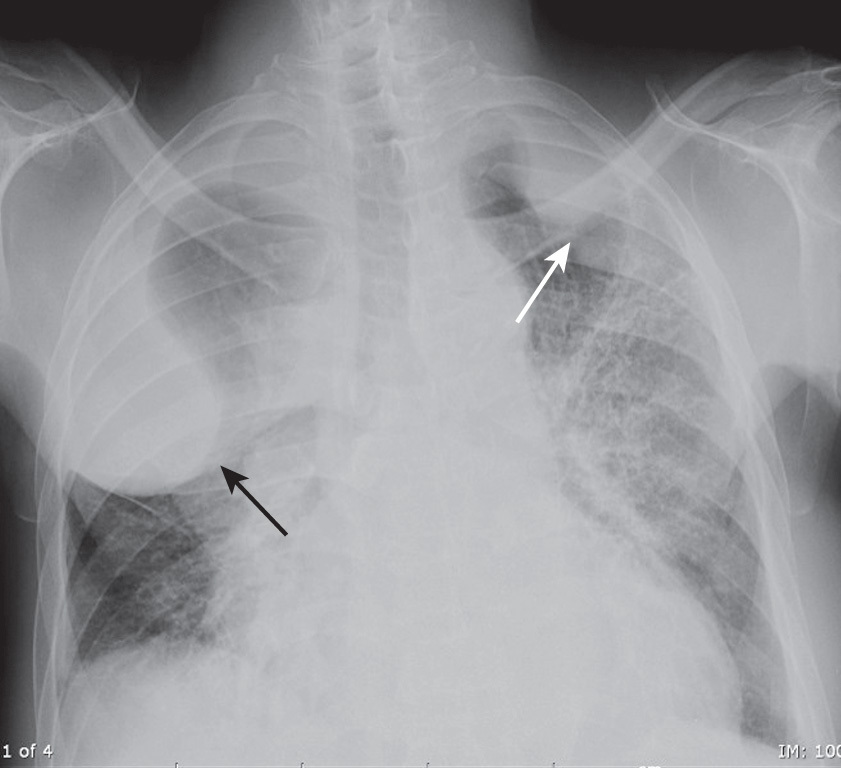

What is going on in this CXR?

These radiographs show atelectasis of the right middle lobe

You can tell that this is atelectasis rather than a consolidation by the downward displacement of the minor fissure

Fissures move towards a collapsed lobe, as do the trachea and heart, and the ipsilateral diaphragm.